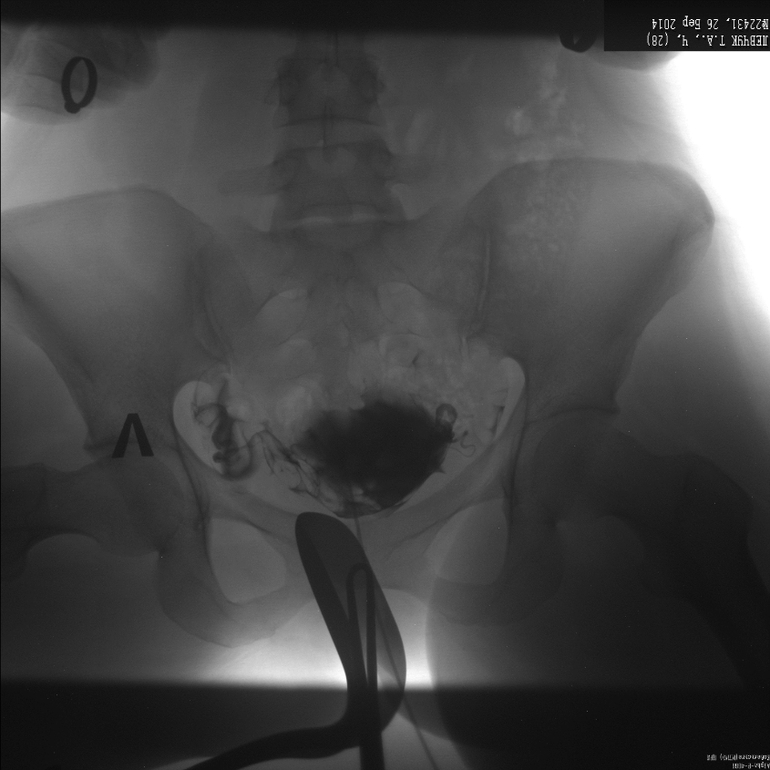

Метросальпингография, посмотрите, неужели все так плохо?

заключения нет, просто сказали, что правая проходима, а левая нет, и трубы тонкие, длинные и закрученные, на лапару отправляют!